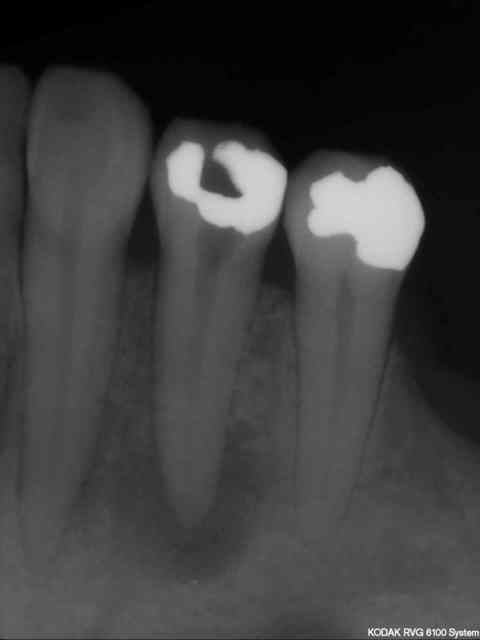

Patiente consulte avec une cellulite carabiné sur 44; trépanation -antibio, hydoxyde de calcium à plusieurs reprises puis traitement endo définitive.

Après tous ces traitements, je ne pense pas que j'arriverai finalement à la sauver car un nouvel épisode infectieux s'est encore déclaré.

Trois mois séparent les deux radios.

Je ne suis pas tres sur ,mais il me semble qu'il ya un debut de changement positif a la radio.Est ce qu'il te semble possible de patienter encore?